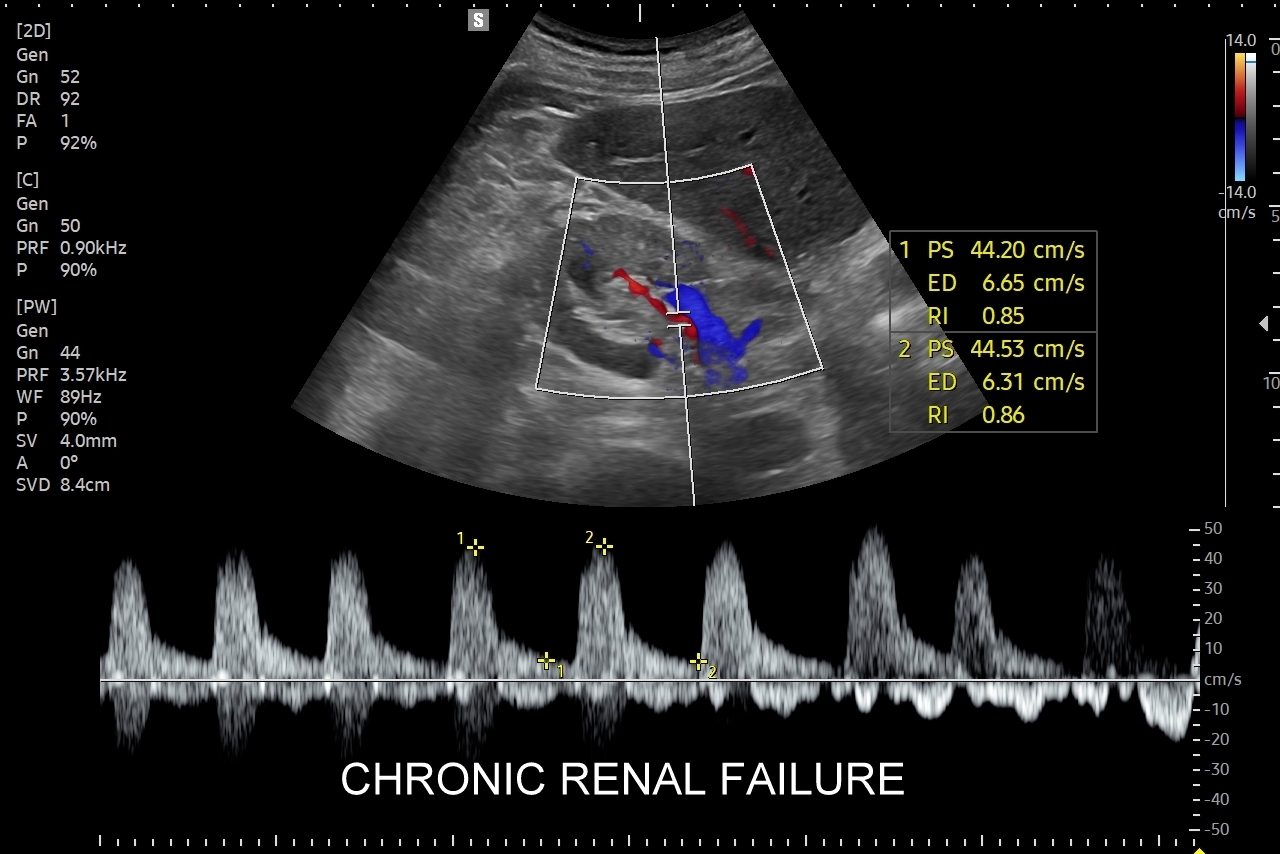

Doppler przepływów nerkowych (USG przepływy nerkowe) jest połączeniem badania obrazowego USG z badaniem funkcjonalnym nerki, jej naczyń tętniczych i żylnych oraz globalnie stanu układu krążenia. Najczęstszym wskazaniem do wykonania USG Doppler tętnic nerkowych, będącego częścią USG Doppler przepływów nerkowych, jest nadciśnienie tętnicze i poszukiwanie jego przyczyn w postaci zwężenia tętnic nerkowych, które mogą wystąpić w odcinku przednerkowym, jak i wewnątrznerkowym. Wykonanie oceny dopplerowskiej nerki jest szczególnie ważne w przypadku wystąpienia nadciśnienia tętniczego u osób młodych lub u dzieci.

Inne wskazania do przeprowadzenia diagnostyki USG przepływów nerkowych obejmują ocenę funkcji nerek w przebiegu chorób ostrych oraz przewlekłych, takich jak nefropatia cukrzycowa, glomerulopatie, czy zapalenia kłębuszków nerkowych. Badanie USG Doppler wykonywane jest również przy podejrzeniu zakrzepicy żyły nerkowej i zespołu „dziadka do orzechów”; przy stwierdzeniu obecności żylaków powrózka nasiennego u mężczyzn; żylaków miednicy u kobiet; w sytuacjach, gdy podczas standardowego badania USG jamy brzusznej uwidoczniono patologię nerki (np. guz nerki, marskość); a także przy stwierdzeniu podwyższonych wartości parametrów nerkowych w badaniach laboratoryjnych (kreatynina, mocznik, cystatyna C, potas) oraz w ramach oceny USG nerki przeszczepionej.